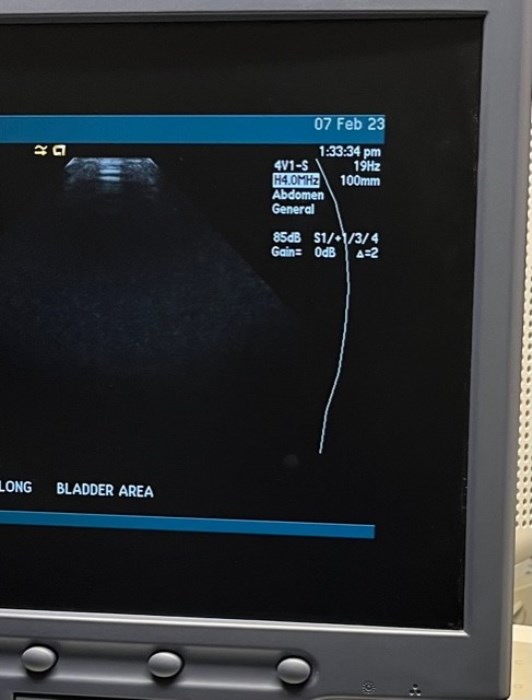

Siemens Sequioa Ultrasound

Pre-owned. In good working condition. Shown as is. Siemens Sequoia Ultrasound. DOM: 2006

Probes: 15L8w, 4V1, 10V4, 6L3, 4C1